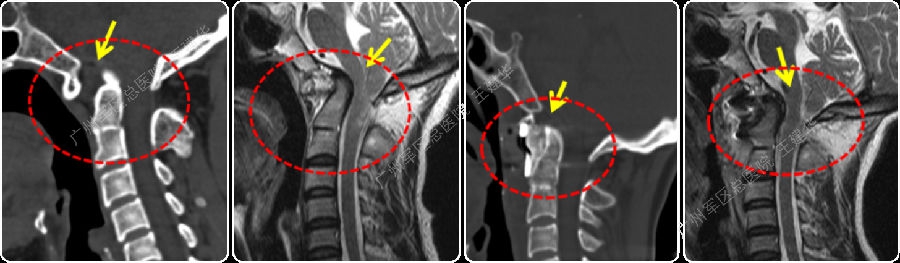

不稳定型颅底凹陷症(寰枕脱位型)

4、颅底凹陷症的神经脊髓压迫机制

前方压迫:上抬的斜坡或陷入枕骨大孔的枢椎齿突等结构自前方压迫脑干、延髓

后方压迫:小脑扁桃体疝造成脑干、延髓后方受压

5、寰枢脱位型颅底凹陷症的特点